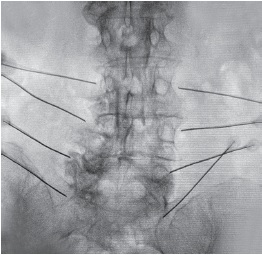

In this group, surgery was performed using Cosman 4G radiofrequency generator. Under radiographic control, 20G guide cannulas with a tip of 5 mm were placed at the levels of interest so that the tip of the cannula was positioned at the center of the transverse process base. Next, a radiofrequency ablation electrode was inserted into each cannula for sensory and motor testing to confirm the correct positioning. If necessary, the position of the guide cannulas was adjusted under radiographic control (Figure 1).

Figure 1. Percutaneous radiofrequency denervation of facet joints. Radiological intraoperative control of the position of the guiding cannulae